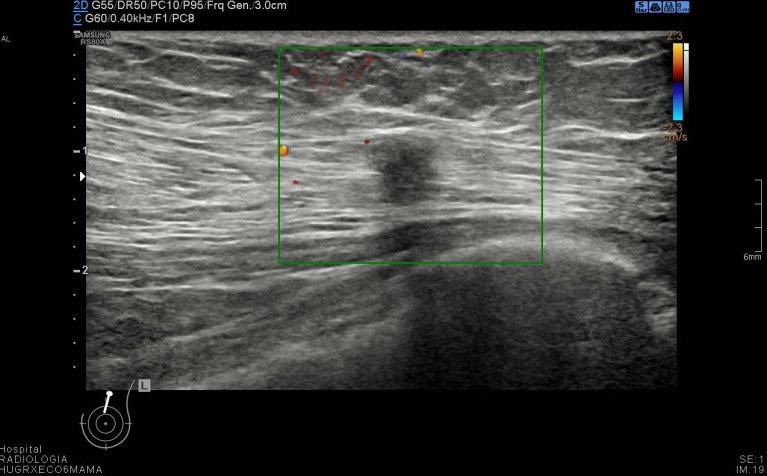

Durante la exploración se observan cambios secundarios a mastectomía bilateral, pero en línea intercuadrántica superior de mama izquierda, en el espesor del musculatura pectoral vi un nódulo hipoecogénico de 6 mm de bordes irregulares (imágenes 2 a 5) que me pareció muy feo, me asusté y aunque no era palpable inmediatamente se lo comenté a la doctora encargada de la exploración, lo calificó de Birads 4C y le pidió resonancia magnética.

Tras los estudios posteriores realizados como ampliación de estudio, arrojaron cambios postquirúrgicos en el pectoral que explicaban la imagen descrita anteriormente y que puedes ver en la imágenes que te he puesto.

Afortunadamente fueron buenas noticias, el resultado fue benigno a pesar de la alta sospecha, a consecuencia de los cambios posquirúrgicos que afectaban a la porción muscular de la exploración ecográfica. Siempre en mamas operadas los cambios postquirúrgicos pueden ofrecer zona llamativas, nosotros siempre atentos y ante cualquier duda lo dejamos reflejado en el pre-informe o se lo contamos directamente a la radióloga responsable, nunca nos quedamos con dudas, siempre documentar los hallazgos correctamente con máxima calidad de imagen, siempre es nuestra carta de presentación.